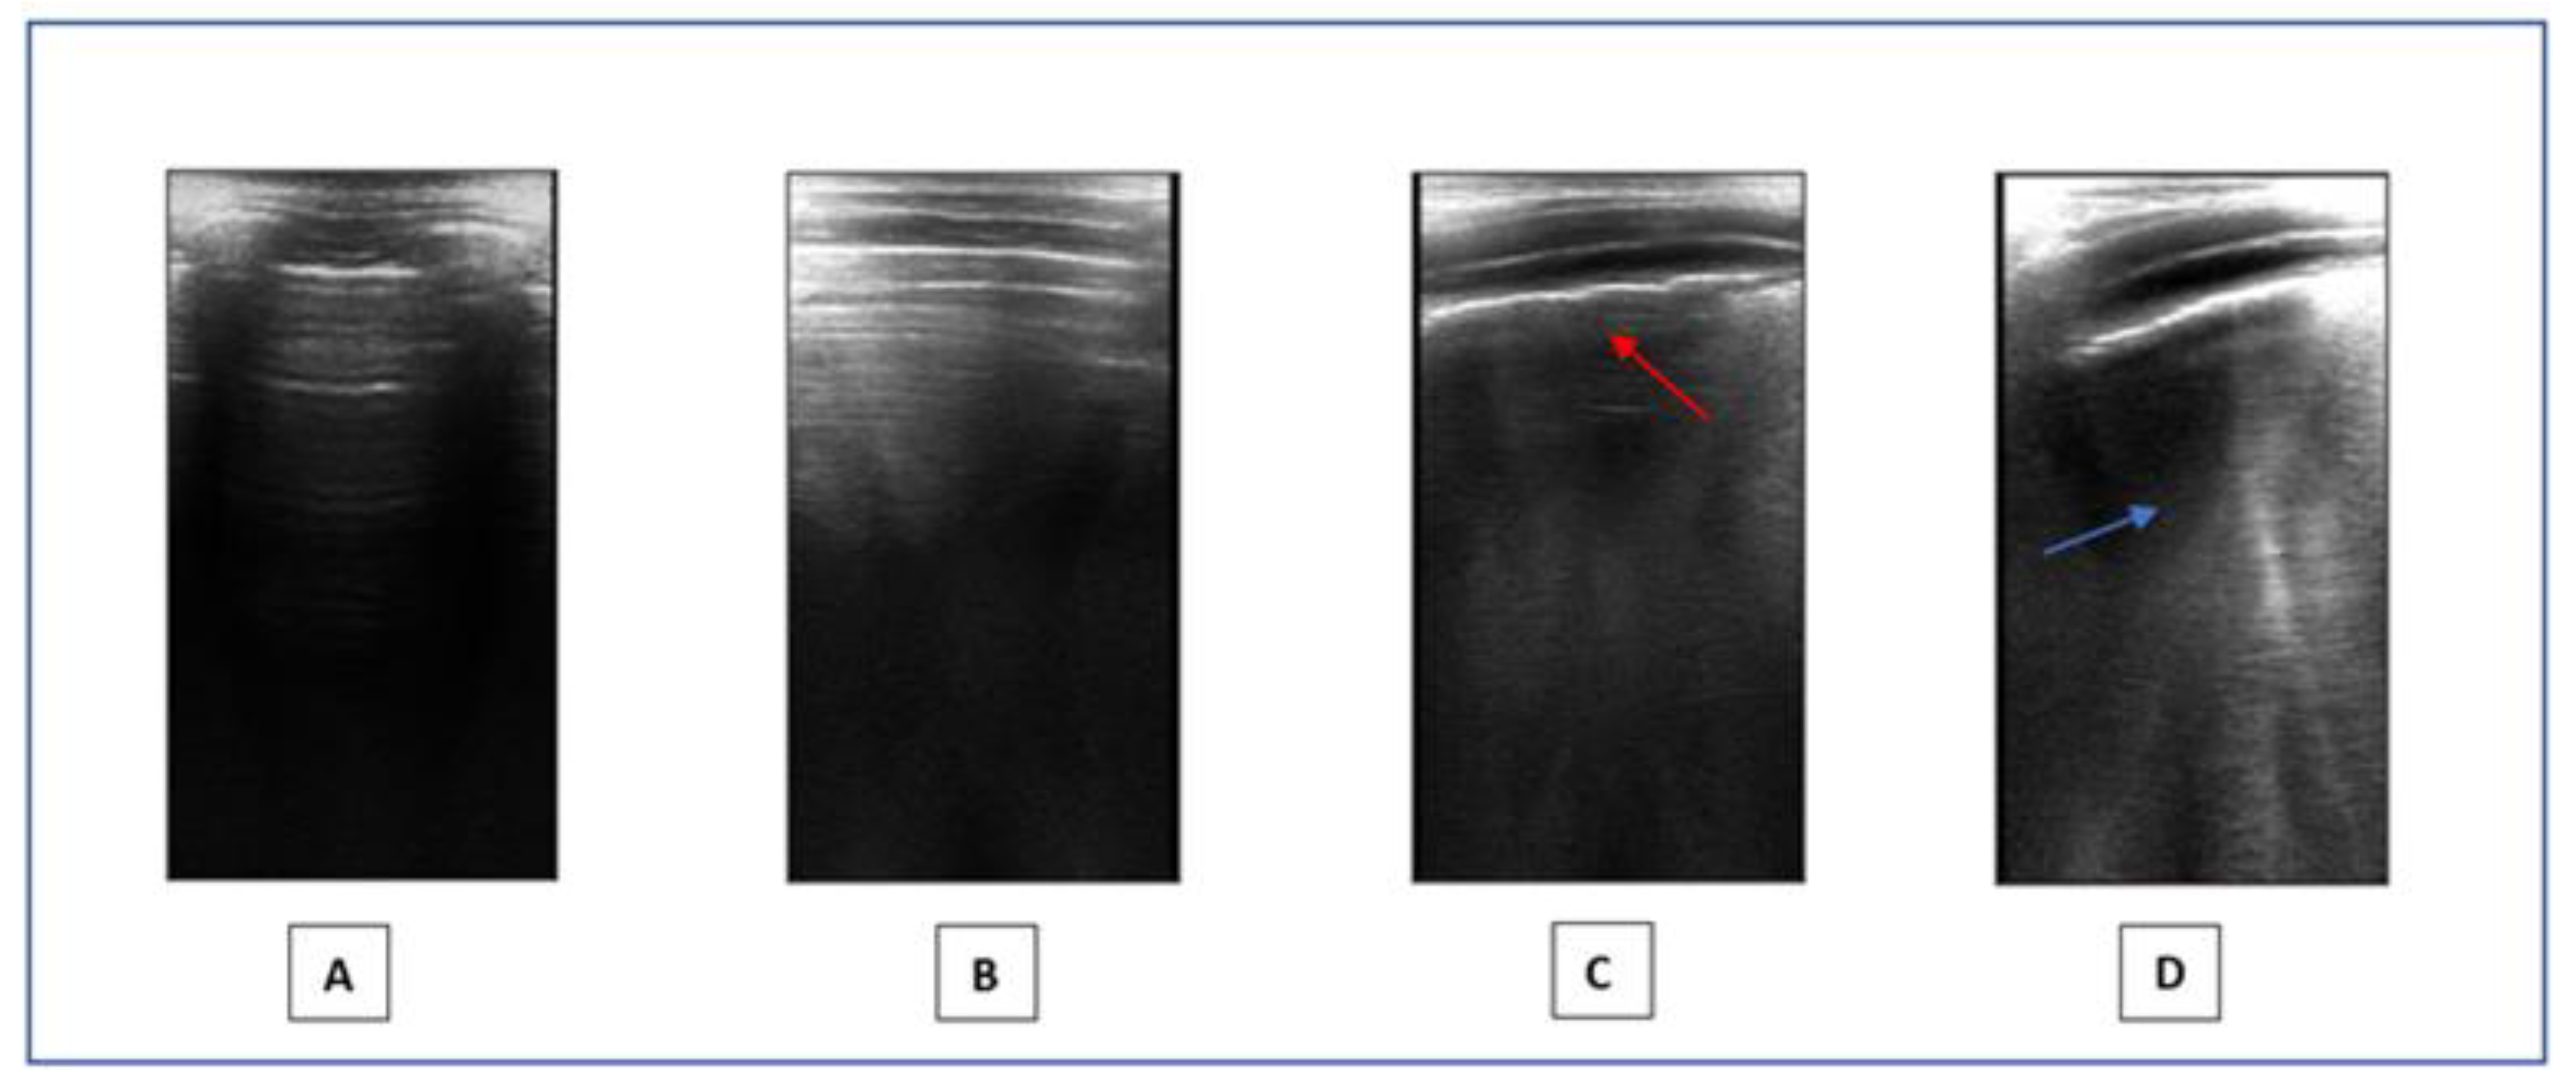

- Lung ultrasound: LUS is a non-invasive method that provides a real-time image of lung structures, enabling doctors to identify early alterations in lung function. The radiation-free approach and portability of ultrasound make it an attractive choice in children, helping to limit exposure to X-rays. LUS has gradually expanded its use to encompass various pediatric applications, including all types of pneumonia, pulmonary embolism, and typical chest and lung diseases in childhood [53]. Lung semiotics consists of artifacts originating from the air/tissue interface and authentic images, like effusions and consolidations [54]. Non-pathological ultrasound images exhibit A-lines and a consistently thin pleural line. Conversely, abnormal images are identified by the observation of three or more B-lines between two ribs in a single scan with the disappearance of A-lines, indicating subpleural interstitial edema, up to a ‘white lung’ picture, consolidations, an irregular or thickened pleural line, and pleural effusion (Figure 1). LUS is a very effective and sensible method for assessing the presence of small pleural effusion. Furthermore, in the diagnosis of childhood pneumonia, lung ultrasound (LUS) is considered as an imaging alternative to computed tomography (CT) scans, as LUS findings demonstrate a significant correlation with those observed in chest CT scans [55]. Nonspecific abnormalities, such as the presence of multiple bilateral B-lines, indicating a reduction in air content, thickening of the pleural line with associated abnormalities, and peripheral consolidation, may be observed on the LUS scans of children with COVID-19 pneumonia [56]. Since the early stages of the pandemic, LUS has demonstrated to be a helpful tool to assess lung conditions, monitor any changes over time, and guide therapeutic decisions in both adults and children [57,58,59,60,61]. The LUS in this study was conducted using a linear probe. We adhered to a standardized approach regarding acquisition protocol, as previously outlined by Volpicelli et al. [62]. We examined a total of 12 thoracic areas: 2 anterior, 2 lateral, and 2 posterior areas on each side. Based on the severity of the findings, a numerical score between 0 and 3 was assigned: 0 = normal; 1 = irregular pleural line with less than three B-lines between two ribs in a single scan; 2 = irregularities of the pleural line with more than three B-lines between two ribs in a single scan; 3 = areas of consolidations or ‘white lung’. Each LUS was performed by the same doctor, Dr. A.K., who is a pediatrician and a certified expert operator in pediatric lung ultrasound.

Figure 1. LUS. (A,B): Normal images. (C,D): Pathological pattern: irregularities of the pleural line (red arrow) and presence of coalescent B-lines (blue arrow).